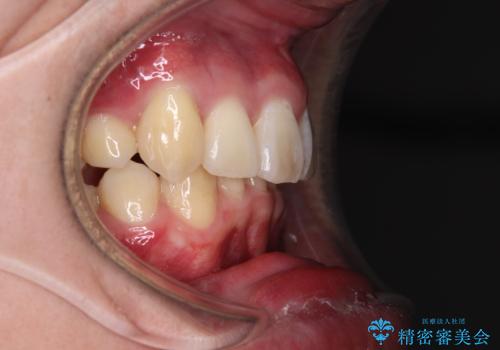

- 八重歯を気にして来院された患者様です。

顕著な上顎の八重歯とディープバイトであったため、上顎の左右第一小臼歯を抜歯することとしました。

犬歯歯根の位置や奥歯の咬み合わせから、ワイヤー装置での治療を強くおすすめいたしましたが、ご本人の強い希望により、妥協的な仕上がりとなることを了解いただき、インビザラインにて矯正治療を行うこととしました。

インビザライン単体で、左右ともに移動の難しい位置に歯根のある犬歯を整えるのは困難と判断し、補助装置を併用することとしました。

ディープバイトや奥歯の咬み合わせなど、インビザライン矯正では限界がありワイヤー装置での治療に及ばない仕上がりとなりました。

ただし、患者様としては八重歯や、それに伴う唇の閉じにくさが改善されたとのことで、納得いく状態での治療終了となりました。